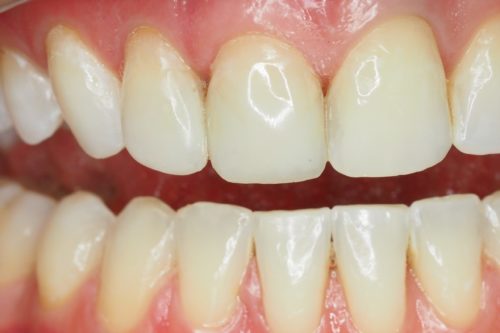

Usunięto stare wypełnienia, opracowano ubytki i wykonano estetyczną odbudowę korony zęba materiałem kompozytowym